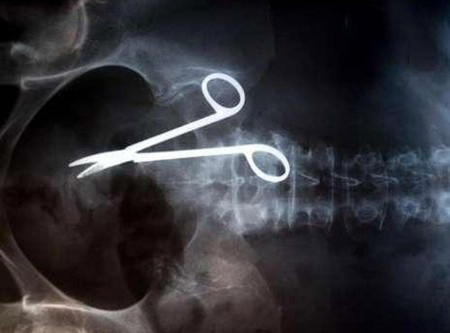

İnanılmaz röntgen filmleri - Resim: 3

İnanılmaz röntgen filmleri görenleri çok şaşırtıyor